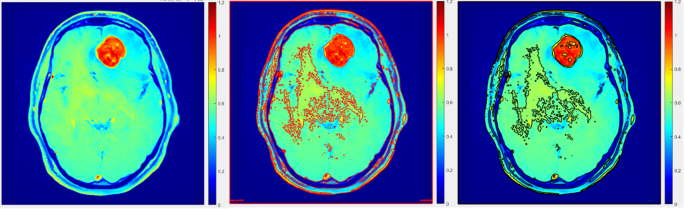

To enhance the precision of tumor delineation in PET/MRI imaging, it is essential to refine the imaging process by excluding structures such as the skull bone and meninges. As shown in Fig. 2, this refinement involves copying the PET delineation onto the MRI image to define initial boundaries (Fig. 2a and b). Subsequently, the MRI is employed to exclude the skull bone and meninges from the region of interest (ROI) (Fig. 2c). The delineation is further enhanced using adaptive thresholding techniques (Fig. 2d). These refinements are critical for achieving accurate boundary definitions and improving diagnostic precision.

This adaptive thresholding methodology, distinguished by its intrinsic adaptability to account for spatial variations in image illumination, proved to be remarkably robust and well-suited for the PET dataset under investigation. Unlike fixed threshold approaches, which faltered in the face of inherent spatial differences in image illumination, the adaptive thresholding method adeptly responded to such variances, facilitating accurate and refined segmentation outcomes. Notably, the adaptive thresholding algorithm was applied to the initial rough delineation of the regions of interest (ROIs), as visually depicted in Fig. 5.

These noteworthy findings not only contribute valuable insights to the existing body of knowledge pertaining to PET imaging data and tumor volume estimation through image segmentation but also hold substantial promise in informing and shaping future endeavors within this domain. Segmentation accuracy plays a critical role in the precise delineation of tumor boundaries in imaging studies. As demonstrated in Fig. 5, a transaxial slice comparison highlights the difference between traditional and adaptive thresholding methods. The adaptive approach shows improved accuracy in defining tumor regions, underscoring its potential for enhancing imaging precision and clinical decision-making.